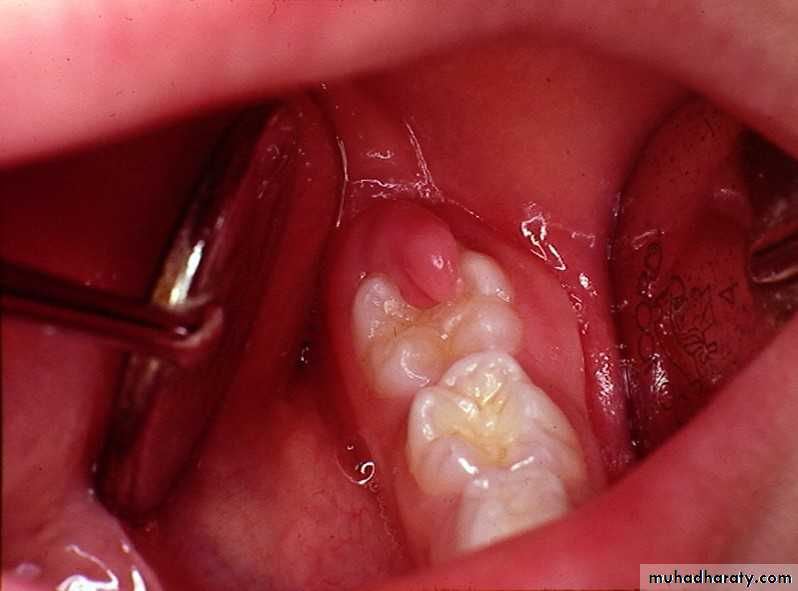

Periodontal abscesses are associated with poorly localized dull pain, adjacent teeth are tender, clenching the teeth, which are usually vital, characteristically brings relief. Mobility of teeth, pathologic sinuses, and evidence of periodontitis are often presentPericoronitis :

Pericoronitis produces rapid onset of soreness or pain in the soft tissues surrounding the crown of a partially irrupted tooth.In the case of impacted third molars particularly the lower ones this soreness is a associated with pain on swallowing and trismus these symptoms are particularly sever in cases of acute pericoronitis. Subacute pericoronitis Is also associated with soreness, pain on swallowing, and trims but their degree severity is milder than that of the acute phase of the disease.